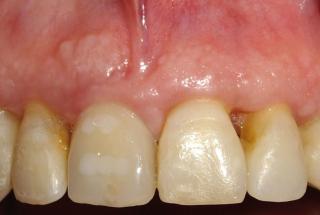

Clinical cases

MPI closely monitors clinical cases in the market to ensure their correct functioning and successful outcome.